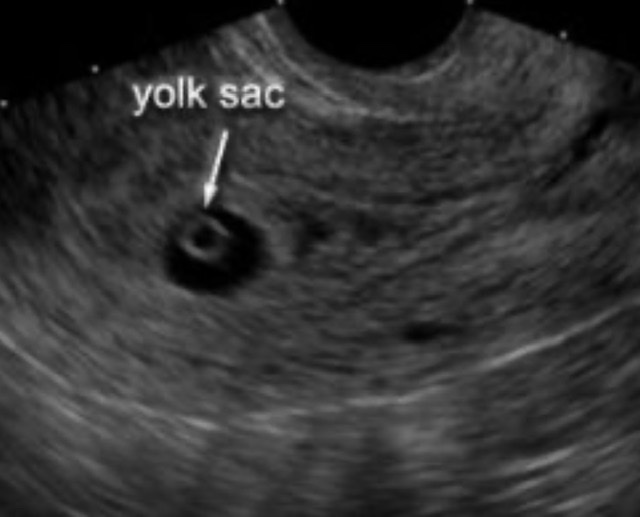

There was a gestational sac and a yolk sac…but there was no fetus. One had not developed. She told me I likely have a Blighted Ovum and I may expect to miscarry. It happens in 50% of miscarriages. She told me that this happens frequently, and while it’s not great news, I should know it’s natural and unavoidable. She explained that it’s due to chromosomal abnormalities. I think I zoned out at this point. She said, “Do you have any questions?”